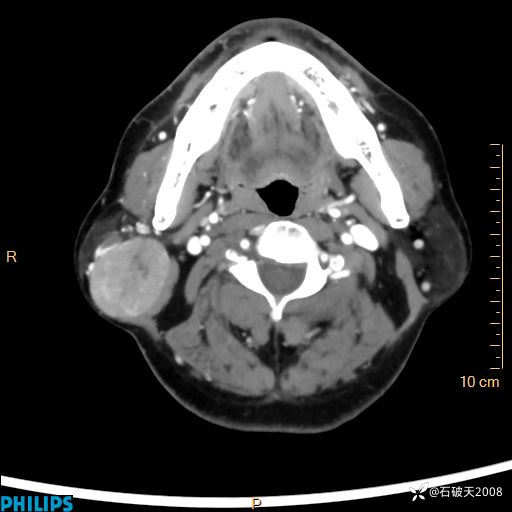

静脉期